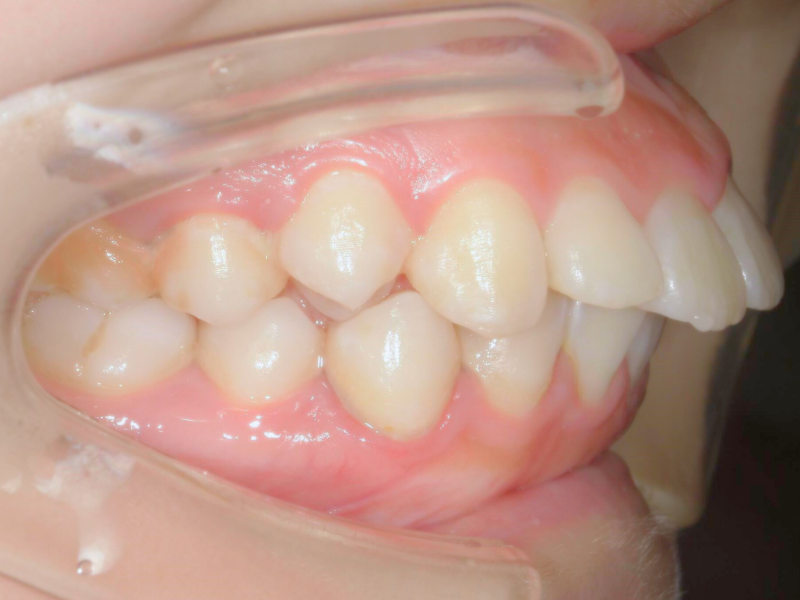

30代、女性、マウスピース

| 施術内容 | 主訴:下の前歯が凸凹で気になる 詳細:マウスピース矯正を装着しての歯並び改善 |

| 治療期間 | 6ヶ月(9/2現在 治療終了) |

| 費用 | マウスピース12枚コース 32万(税込352,000円) |